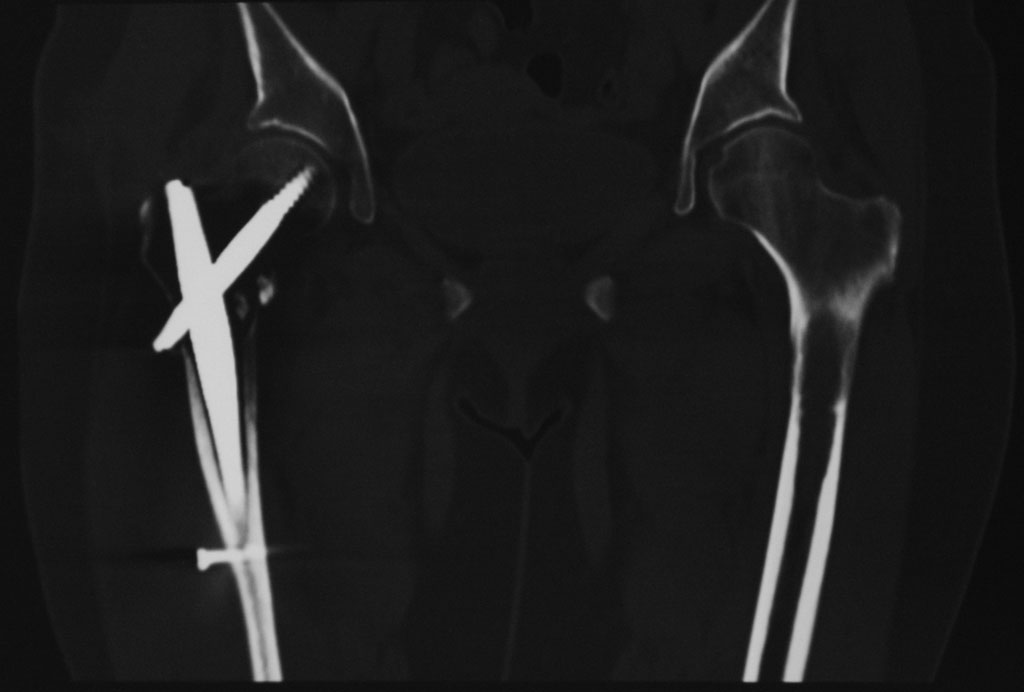

Добрый день. 2,5 месяца назад пациентке по поводу патологического чрезвертельного перелома правой бедренной кости (киста) был выполнена закрытая репозиция и БИОС гамма-гвоздем Stryker с заполнением полости Hydroset.

Гистологическое заключение: участки остеонекроза,хроническое воспаление. На этой неделе больная обратилась с жалобами на боли в области левого тазобедренного сустава. Со стороны оперированной ноги жалоб нет. Проведенное рентгенобследование выявило наличие полостного образования в проксимальном метадиафизе левой бедренной кости, перелом наружной стенки. Планируем выполнить БИОСлевой бедренной кости по методике аналогичной на правой ноге и этому случаю Какой фиксатор выбрать: длинную гамму или универсальный бедренный гвоздь?

Rg-грамма

Кликните для загрузки файла IMG_5485 copy_.jpg